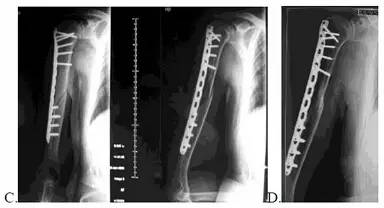

MIPPO 技术:A:在骨折两端分别做切口,将钢板从骨折远端插入通过近端调整位置后固定;B:术后皮肤切口;C:术后 X 线片,可见不追求精确对位,不对骨折端进行分离而保护了血液供应;D:术后复查,骨折线模糊,骨折愈合。